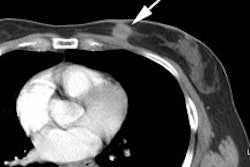

with whole-brain radiation. Radiation injury occurs in 5% to 37% of cases and

can be difficult to differentiate from residual or recurrent malignancy by MRI.